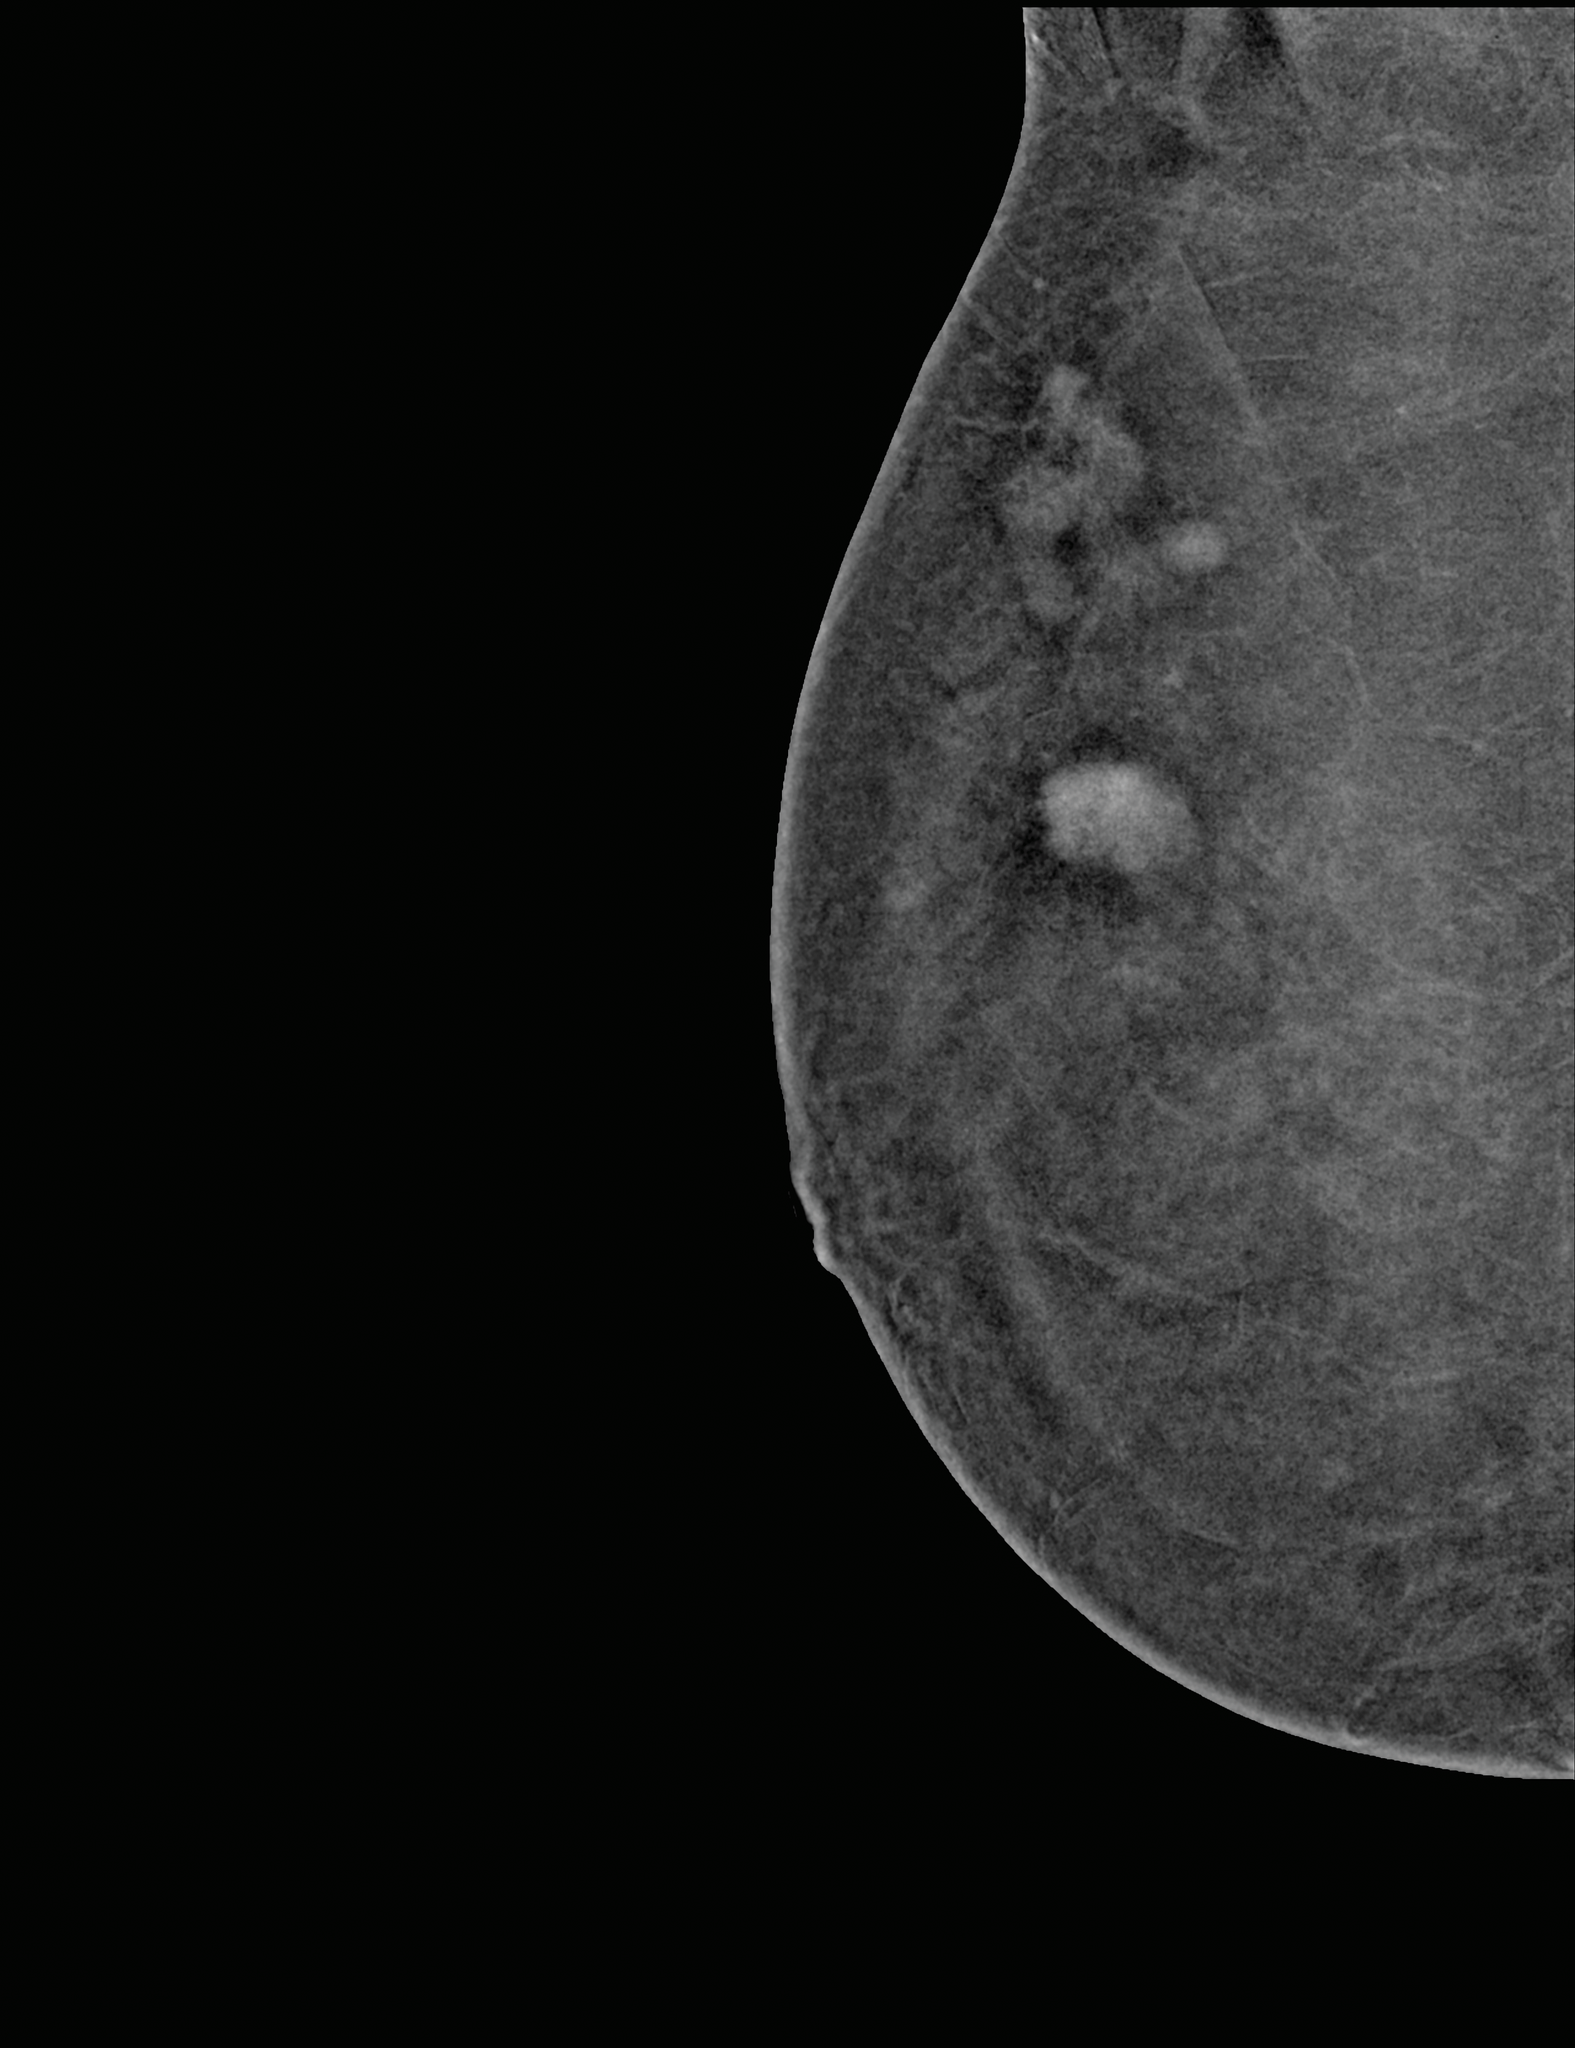

A Contrast Enhanced Mammogram (CEM) is similar to having a conventional mammogram but with the addition of a contrast enhancing IV dye containing iodine (the same dye as used in CT scans) to make it easier to characterise breast abnormalities and detect cancers that may not be visible in a standard mammogram. A doctor may refer you for a Contrast Enhanced Mammogram if you are at an increased risk of developing breast cancer, have dense breast tissue, or as an alternative to MRI.

Contrast Enhanced Mammography allows clinicians to see certain lesions and abnormalities that conventional mammography cannot detect – especially in patients at increased risk of breast cancer or who have dense breasts or implants.